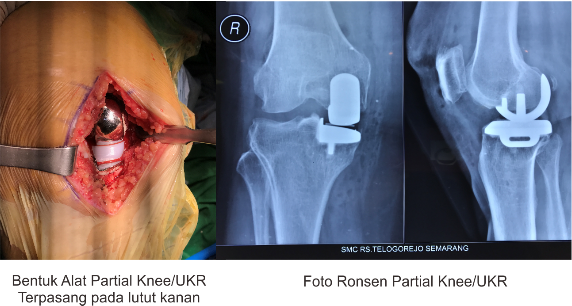

‘Penggantian Sendi Sebagian’/Partial Joint Replacement adalah suatu prosedur tindakan penggantian sendi yang dilakukan pada bagian sendi tertentu yang rusak berat (sebagian), yang memberikan rasa nyeri yang mengganggu, tidak kunjung membaik dengan pengobatan, ataupun memberikan fungsi yang buruk bila bagian sendi tersebut dipertahankan. Contoh penggantian sendi sebagian tersebut diantaranya: ganti bonggol sendi dan ganti sebagian sendi lutut (unicondylar knee replacement).

Penggantian bonggol sendi panggul umum dilakukan pada usia lanjut dimana terjadi kerusakan pada bagian kepala tulang paha (bonggol) tanpa melibatkan kerusakan mangkok sendi atau pada kasus patah bergeser yang melibatkan bonggol tulang paha, sedangkan penggantian sendi sebagian pada lutut (unicondylar knee replacement) dapat dilakukan pada sendi lutut yang rusak pada setengah sisi dalam bagian sendi.

Khusus untuk penggantian sendi lutut sebagian yang dikerjakan di SMC/RS Telogorejo umumnya menggunakan alat desain/produksi negara Inggris dengan teknologi mobile bearing dimana bantalan sendi buatan dapat bergerak mengikuti gerakan permukaan sendi buatan sehingga menambah lingkup gerak sendi dibandingkan versi standar.